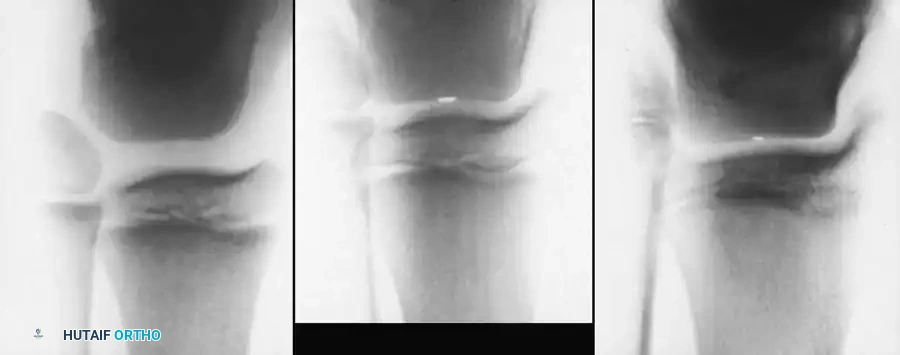

Knee Deformities

Knee deformities typically present as either flexion or extension contractures.

* Extension Contractures: Common in high-level lesions. Treated with V-Y quadricepsplasty if interfering with seating.

* Flexion Contractures: Common in L3-L4 lesions due to unopposed hamstrings. Contractures >20 degrees interfere with bracing and ambulation.

Knee Flexion Contracture Release

Surgical Management:

Mild contractures are managed with hamstring lengthening and posterior capsulotomy. Severe, rigid contractures in older children may require a distal femoral anterior closing-wedge extension osteotomy.

Distal Femoral Extension Osteotomy